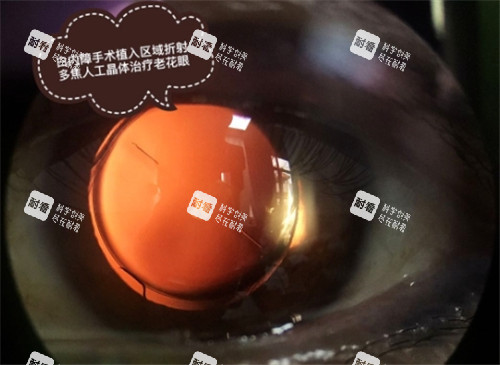

老花白内障手术主要针对同时患有白内障和老花眼的患者,通过植入功能性人工晶体,实现术后远、中、近视力兼顾的结果。手术方式分为飞秒激光辅助与常规超声乳化两种,费用因晶体类型而异:

飞秒激光辅助:飞秒套包费用为8000元/眼,属自费项目。该技术通过激光制作切口和撕囊,提高手术精密度,减少并发症,适合对可靠性要求高的患者。